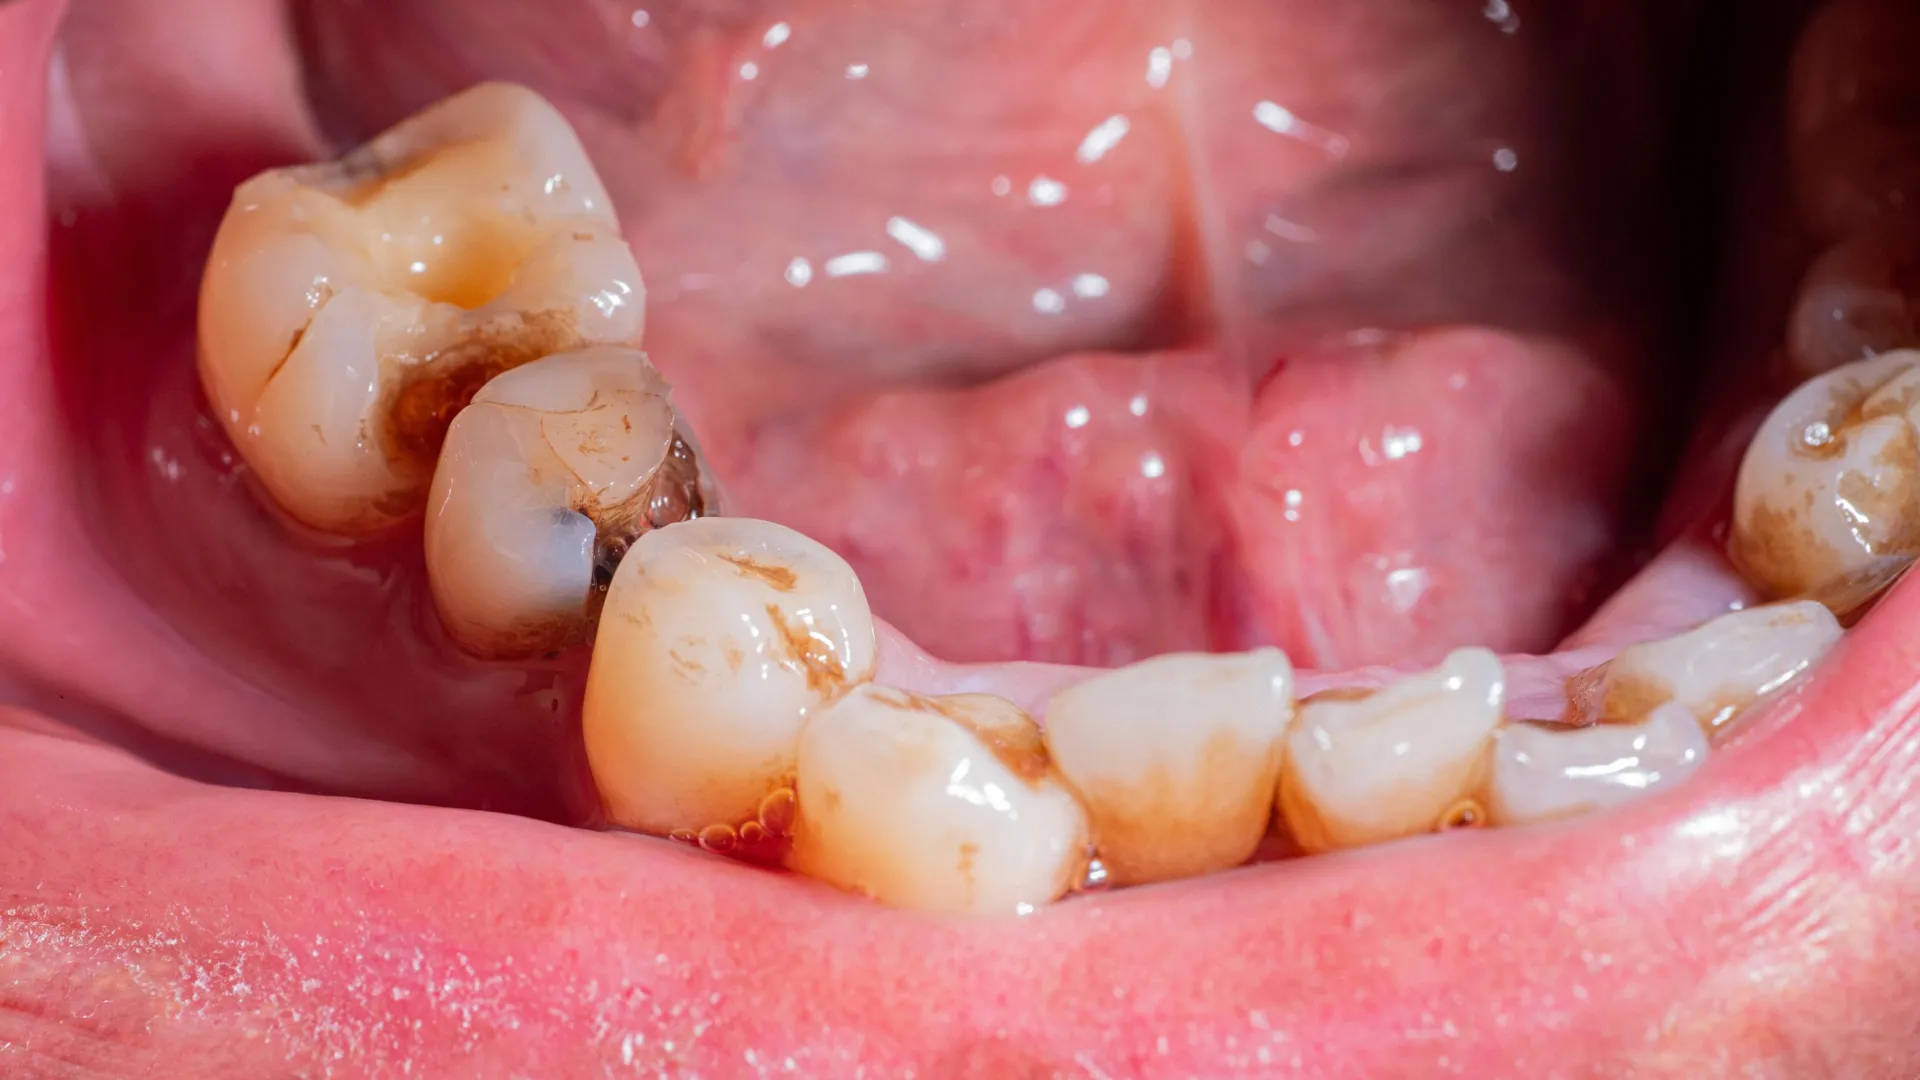

Ms. Silva further explained the precise mechanism by which CANECPI-5 exerts its protective influence. She noted that the protein exhibits a direct affinity for tooth enamel, facilitating its adhesion and thereby enhancing the resistance of teeth to the corrosive actions of acids produced by oral microorganisms. This direct binding capability is central to its protective function. The study further revealed that the efficacy of CANECPI-5 is significantly amplified when it is formulated in conjunction with fluoride and xylitol, two well-established agents in dental caries prevention. In experimental settings, the artificial saliva formulation, when applied as a spray, effectively suppressed bacterial activity and demonstrably slowed the rate of tooth demineralization. This latter process, the loss of essential minerals like calcium and phosphate from tooth enamel, renders teeth more susceptible to the formation of cavities.

The implications of this research are particularly profound for patients undergoing radiotherapy for head and neck cancers. This demographic frequently experiences radiation-induced damage to their salivary glands, leading to a severe reduction or complete cessation of saliva production. The resultant xerostomia not only causes significant discomfort but also creates a highly conducive environment for the rapid development of aggressive dental caries, for which effective preventative or therapeutic products are currently scarce. This new artificial saliva offers a much-needed therapeutic avenue for these vulnerable individuals, potentially alleviating the severe dental sequelae of their cancer treatment.